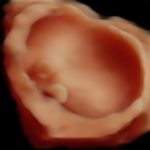

4D/5D/HD Ultrasound Gallery

Gallery